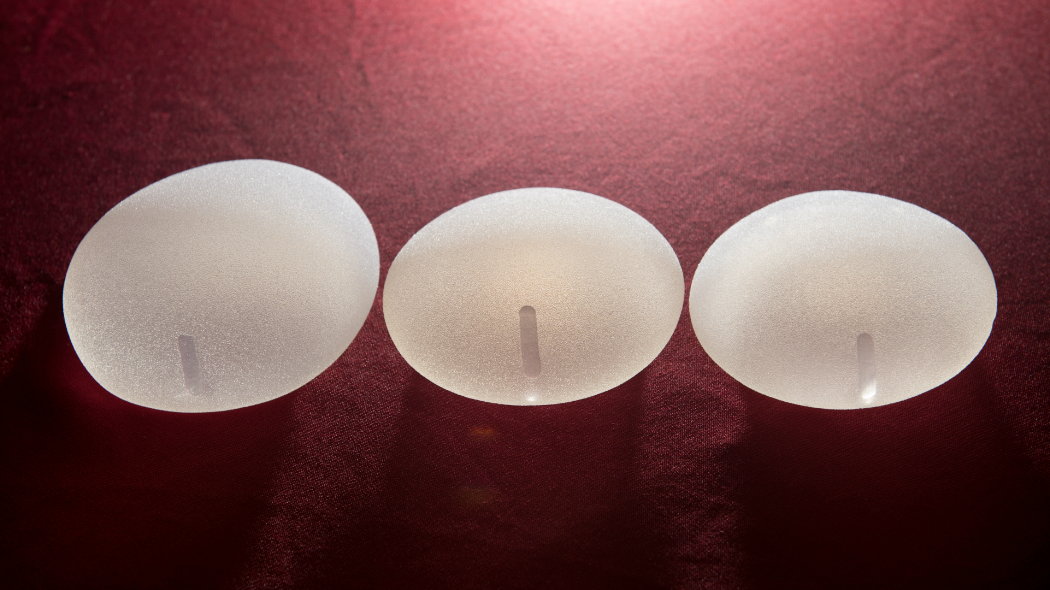

Анатомические импланты Eurosilicone

Раздел: Визуальный дайджест